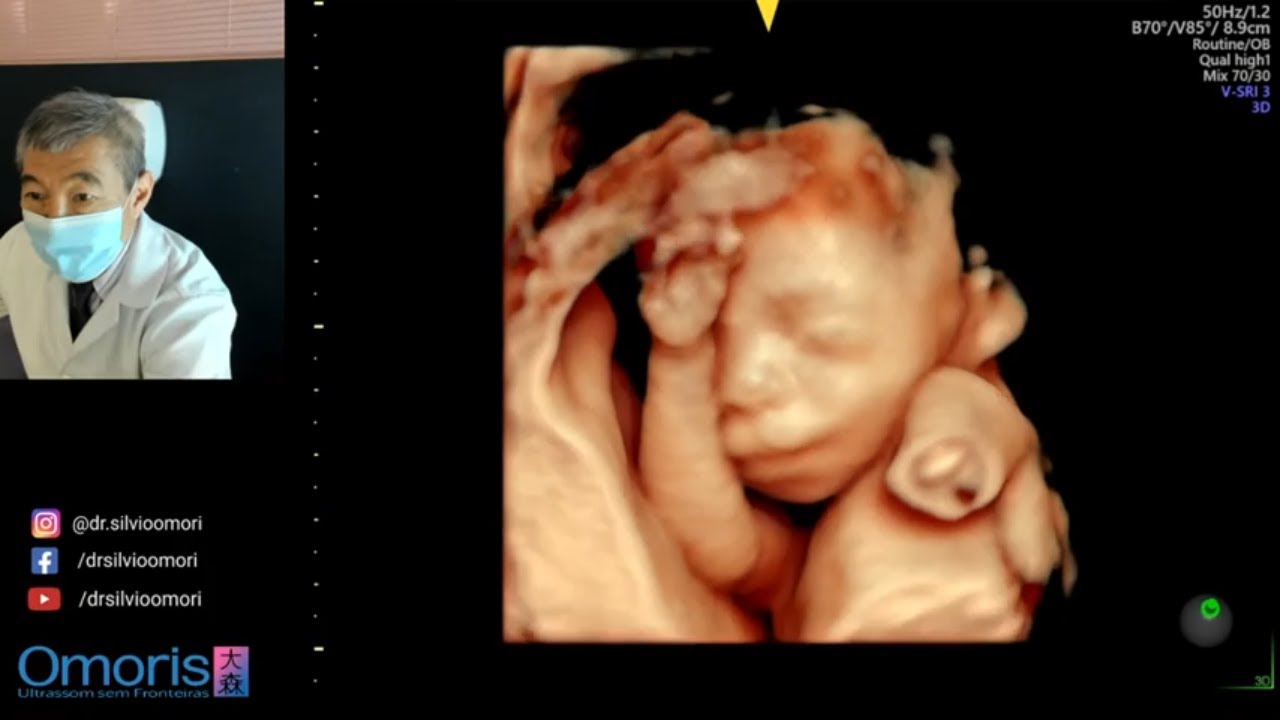

MENINO OU MENINA ? Gravidez 21 semanas.

Описание: MENINO OU MENINA ? Gravidez 21 semanas.